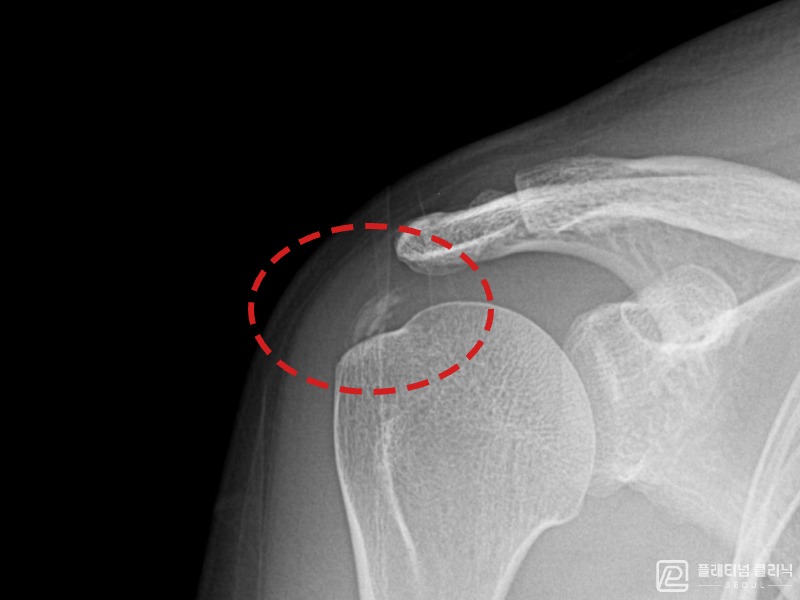

[촬영시기:21.10.21~21.10.30]

[석회분쇄흡입술] 우측 어깨 통증과 운동 제한으로 일상생활이 불편해진 30대 여성 환자로, X-ray에서 우측 극상근건 내 석회 침착이 확인되어 석회분쇄흡입술을 시행하였습니다.